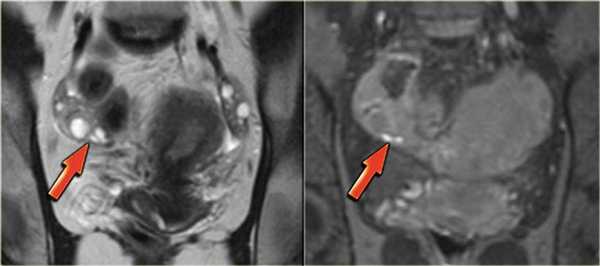

На Т1 и Т2 взвешенных томограммах у пациентки с эндометриозом визуализируются «целующиеся» яичники, расположенные вплотную друг к другу из-за множественных спаек. Также видны небольшая геморрагическая киста в левом яичнике и поверхностная геморрагическая бляшка, дающие гиперинтенсивный сигнал (красные стрелки)